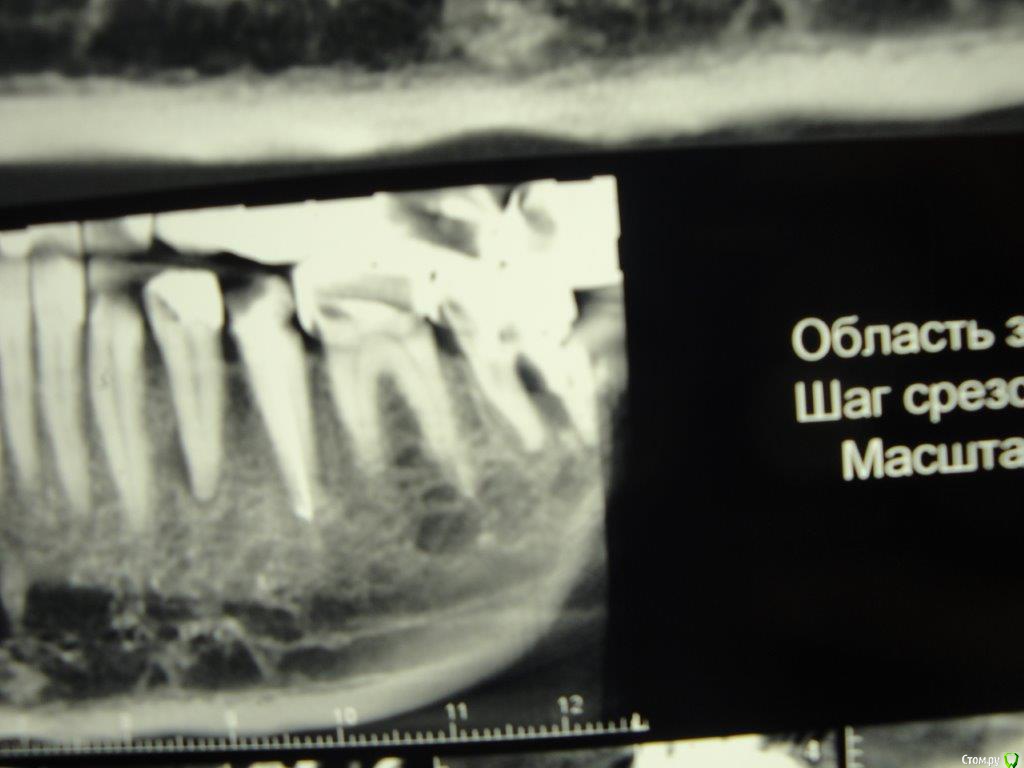

Коша Опубликовано 26 апреля, 2016 Поделиться Опубликовано 26 апреля, 2016 Здравствуйте!Подскажите пожалуйста!можно ли восстановить 7снизу слева зуб. пару врачей мне сказали, что нужно удалять, но вера в современную стоматологию, еще теплит надежду, что возможно еще можно над ним поработать, и пока оставить его!Зуб не болит, я им жую, но стала образовываться щель между телом зуба и краем коронки.Есть несколько снимков (отрывки с панорамных снимков)- прилагаю их. Ссылка на комментарий